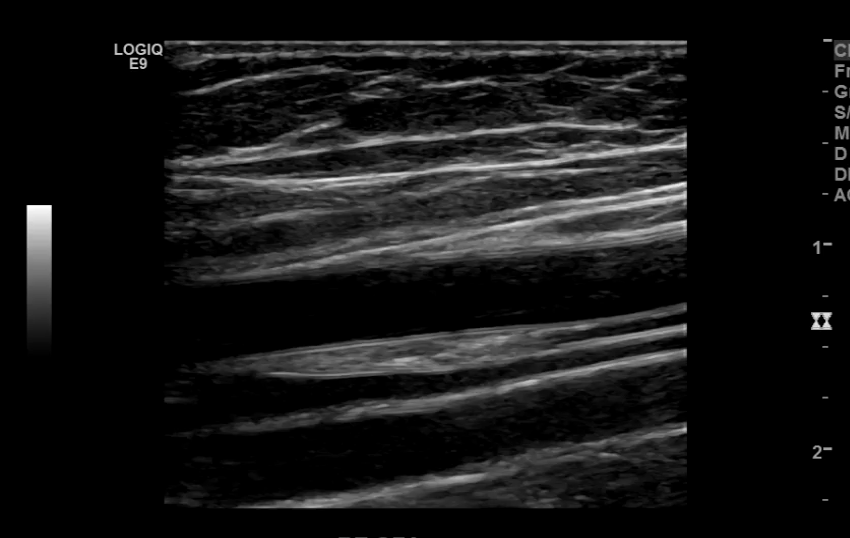

The iliac arteries bifurcate into external and internal iliac arteries (EIA and IIA). The EIA continues caudally turning into the common femoral artery (CFA) which further bifurcates into superficial femoral (SFA) and deep femoral artery (aka profunda femoris). The SFA then converts into the popliteal artery which bifurcates into the tibioperoneal trunk and anterior tibial artery (ATA). The tibioperoneal trunk bifurcates into posterior tibial artery (PTA) and the peroneal artery. The anterior tibial artery descends further to become the dorsalis pedis artery (DPA).

Superficial Femoral Artery